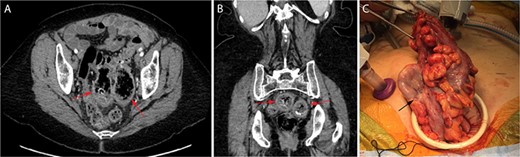

A 68-year-old woman with history of hypertension, breast cancer, gastroesophageal reflux disease, osteoarthritis, hypothyroidism and prior GI bleeding with frequent NSAID use underwent diagnostic colonoscopy to evaluate anemia to 9.6-g/dL refractory to iron supplementation. Prior abdominal surgery included umbilical hernia repair and caesarian section. She denied abdominal symptoms including pain. Colonoscopy identified widespread left-sided diverticulosis and two large, cavernous areas partially filled with dark debris in the sigmoid colon without active bleeding. CT imaging confirmed severe diverticulosis with two GCD arising from the posterior wall of the proximal and mid-sigmoid colon measuring 6.8 × 4.4 × 4.3 cm and 6.1 × 5.2 × 3.9 cm, respectively (Fig. 1A and B). Mild wall thickening and trace, low-attenuation fluid in the adjacent sigmoid mesentery were suggestive of an inflammatory state without evidence of perforation. The patient was appropriately counseled and offered laparoscopic sigmoidectomy.

Cross-sectional CT imaging readily identified the two large GCD (red arrows) on both axial (A) and coronal (B) view. View of the largest GCD (black arrow) during specimen extraction intra-operatively (C).

Intra-operatively, the two GCD were seen extending well into the pelvic cavity with minimal scarring and no evidence of perforation. Sigmoid colectomy was performed to an area of pliable, descending colon and specimen extraction was performed via a Pfannenstiel incision (Fig. 1C) before performing an end-to-end, circular stapled coloproctostomy anastomosis. The patient recovered well, with return of bowel function on post-operative day 4 and discharge home on post-operative day 6. Her anemia corrected with ongoing iron supplementation, and she experienced no complications within 10 months of follow-up.